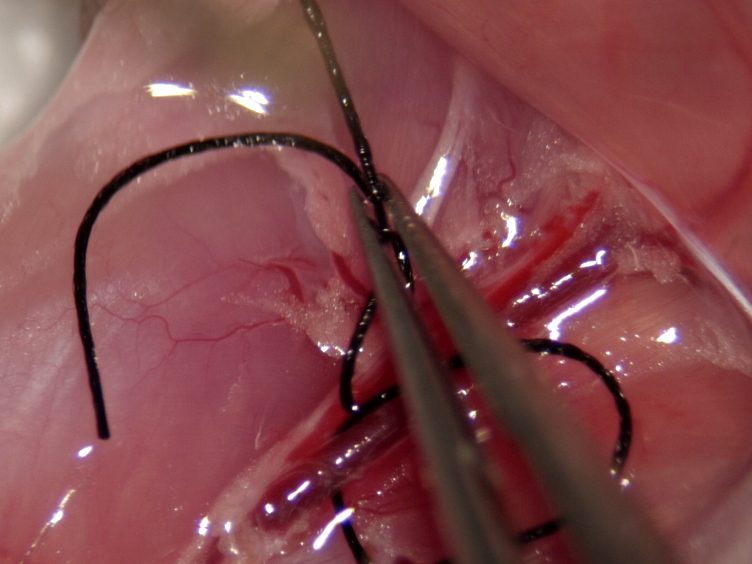

- Surgery and biopsy